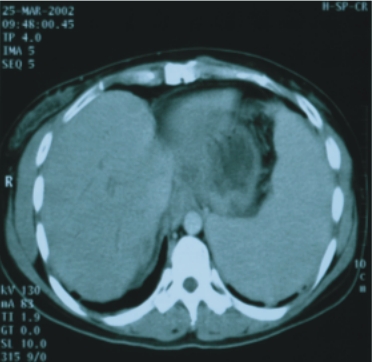

(二)肝內之肝細胞癌及膽道癌:

17例患者(其中膽道癌7例),大部分為無法手術切除或施行動脈栓塞者,其中2例膽道癌曾接受膽管支架置入術。利用此治療技術以增加腫瘤控制率及延長存活時間,同時較傳統放射治療更能保護正常肝臟之功能。平均追蹤時間為23個月。腫瘤反應率(即縮小50﹪以上的機會)85﹪,18個月之存活率75﹪,且無病患因治療而出現肝衰竭。

| 24歲/女性

(肝癌) |

41歲/女性(膽道癌合併肝轉移) |

||

| 89/3/3(治療前) |

89/4/12(治療後) |

88/5/6(治療前) |

88/6/6 (治療後) |

| 腫瘤大小:5x5x4公分

|

完全消失 |

腫瘤大小:4.5x4.5x4公分 |

完全消失 |